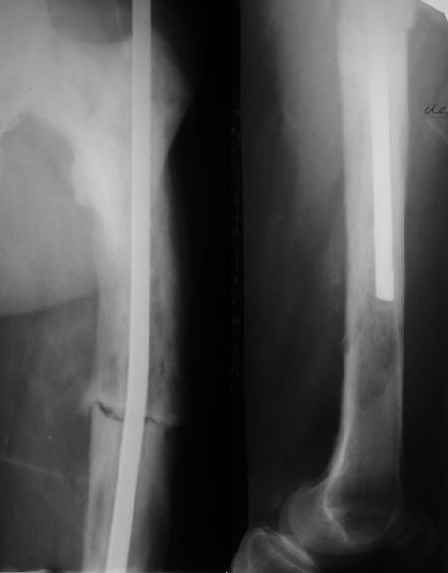

Еще один пример. Пациентка с юга России, прислала рентгенограммы через год. На сегодня прошло 2 г. 8 мес. после операции. Несмотря на не очень убедительный процесс сращения, пациентка ходит. Учитывая остеопороз при Педжете, решили, что динамизировать вообще не нужно.